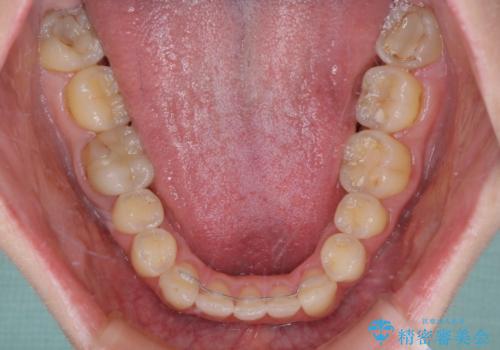

思っていた以上に上顎歯列を後方に移動させることができ、すっきりとした口元に仕上げることができました。